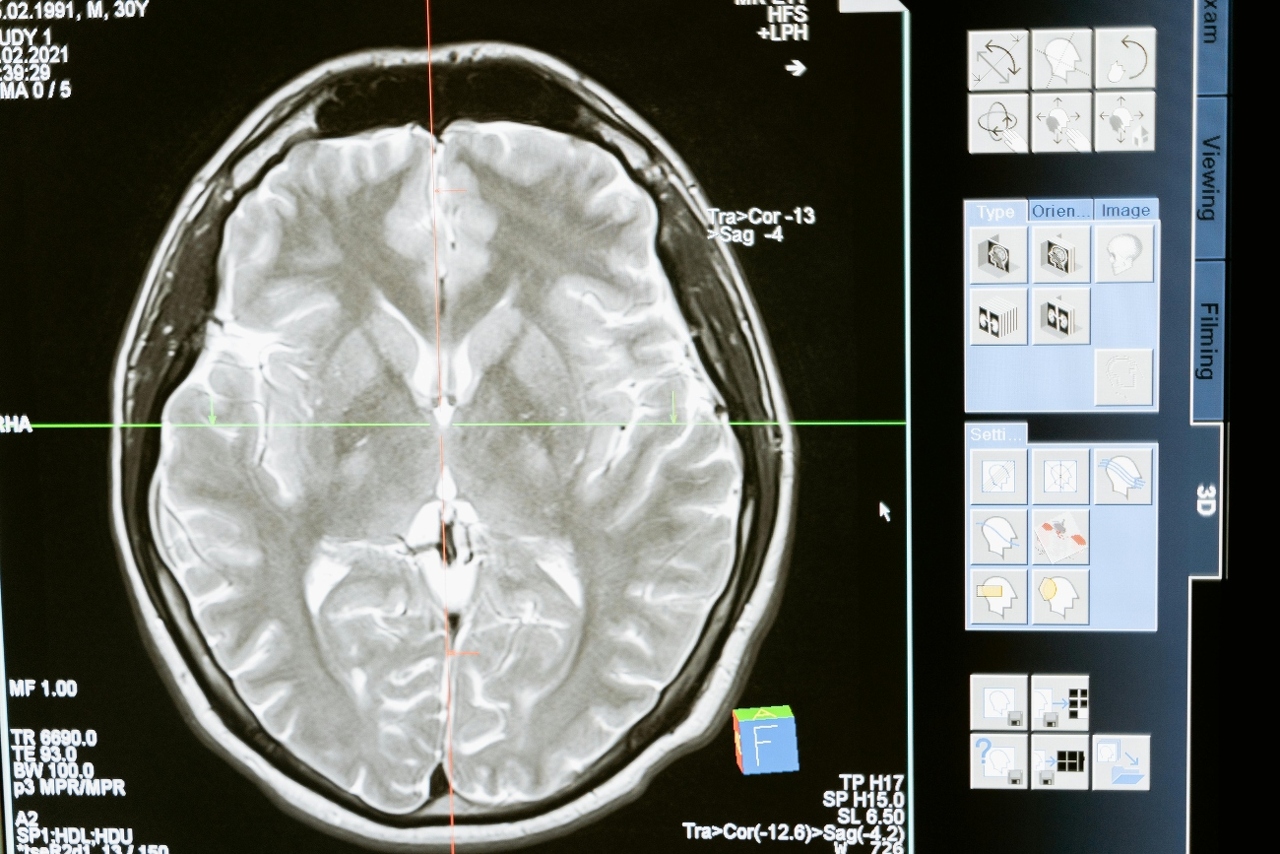

MRI snimanje CP-jeva mozga pokazalo je selektivnu atrofiju i gubitak tkiva upravo u tom području.